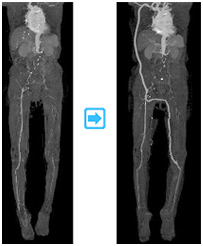

◎CT・MRI検査

動脈硬化の程度、部位を大まかに調べることが可能です。

◎血管造影検査

実際に動脈に造影剤を注入し、血管病変の部位、程度を詳しく調べます。